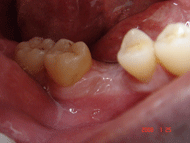

| <症例3> |

| 左下456番に埋伏歯を避けブリッジタイプのハイブリッドセラミック補綴 |